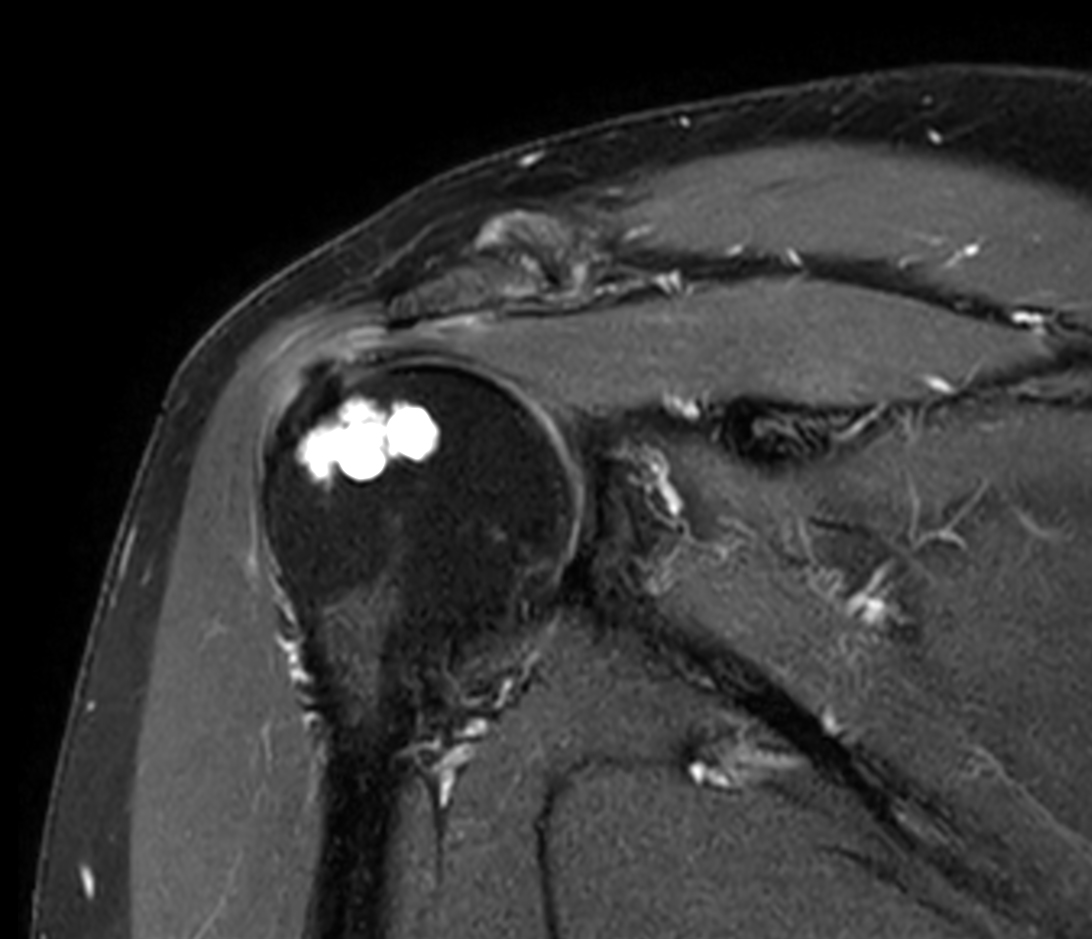

Coronal T2w SPAIR